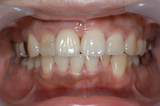

自転車で転倒し前歯が根本から折れてしまい、抜歯に至ったケース

このケースは感染していないので、抜歯と同時にインプラント埋入

埋入後、3か月で終了